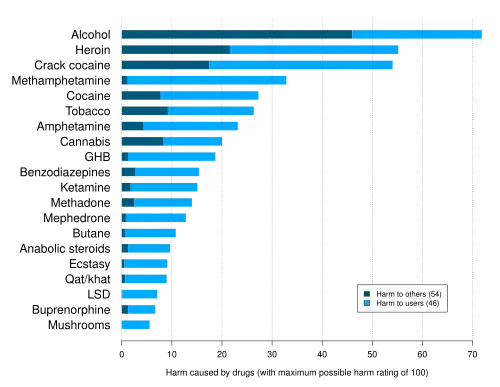

Heroin is classified as a hard drug in terms of drug harmfulness. Like most opioids, unadulterated heroin may lead to adverse effects. The purity of street heroin varies greatly, leading to overdoses when the purity is higher than expected.[59]

- ^ Nutt DJ, King LA, Phillips LD (November 2010). "Drug harms in the UK: a multicriteria decision analysis". Lancet. 376 (9752): 1558–65. CiteSeerX 10.1.1.690.1283. doi:10.1016/S0140-6736(10)61462-6. PMID 21036393. S2CID 5667719.